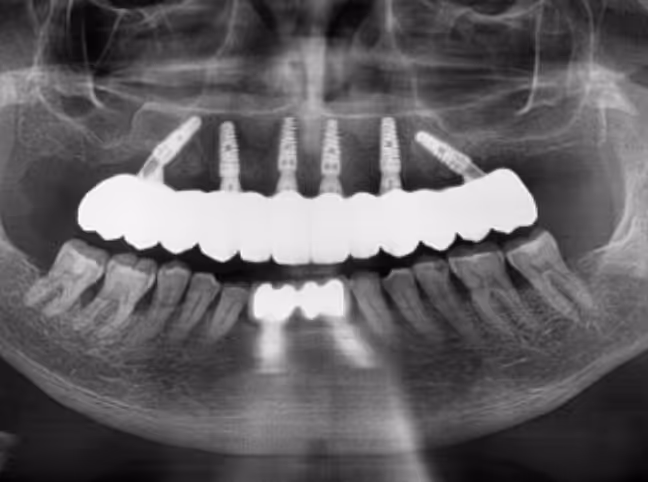

Rehabilitación maxilar completa con implantes Triplo de Eckermann

Implantes angulados con carga inmediata para maxilares atróficos.